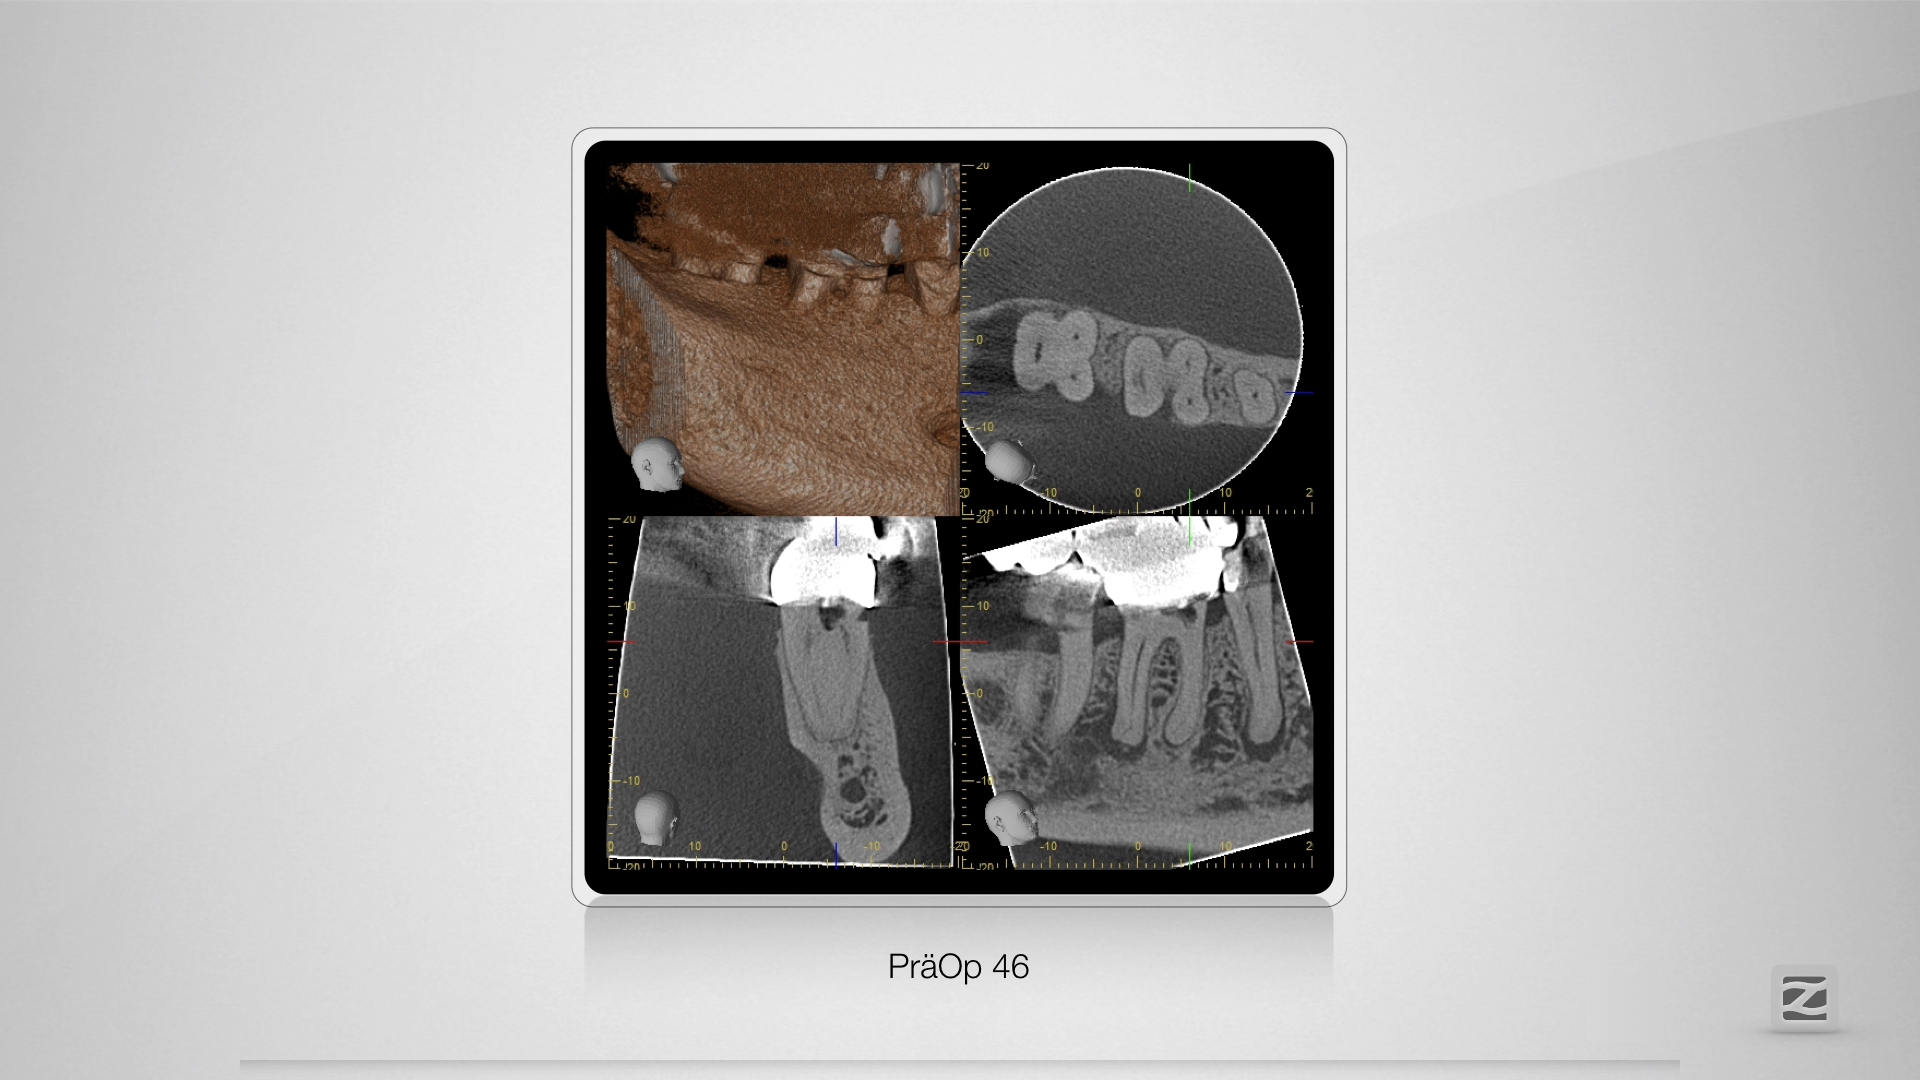

46D.003

Zugang, Zugang, Zugang.